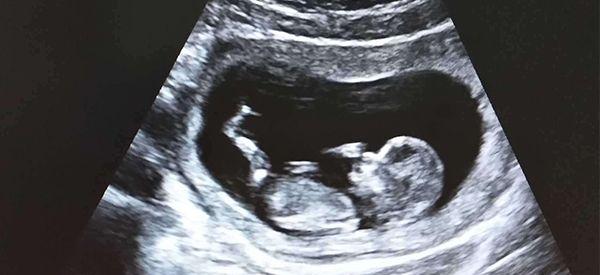

现在怀孕12周,刚做了nt检查,结果显示只有1.8,我还没来得及高兴,婆婆看完却说孩子以后会很聪明,还说nt厚度越薄越聪明,我想知道产检时nt厚度越薄胎儿越聪明是真的吗?

假的,nt的厚度和胎儿是否聪明并没有关系,nt检查只能用来评估胎儿存在唐氏综合征的风险,nt数值越大的话,说明宝宝有可能得唐氏综合症,但是nt值越小的话,就说明宝宝存在异常的可能比较小,和智力是没有关系的。

胎儿的智力和nt厚度没有关系

宝宝的智力只有一部分是遗传的,很大部分还是靠后天的培育,所以不要觉得nt值越低,就代表着宝宝越聪明,这种说法是没有科学依据的,如果nt值比较高的话还会增加自己的心里负担,不利于胎儿发育,所以尽量让自己放松,保持好的心态就好。

并没有,只要小于2.5mm,在nt检查正常范围内就是正常的,说明胎儿患有唐氏综合征的风险比较小,如果超出2.5就要考虑唐氏综合症的可能性,所以一般只要在2.5以内就是健康的,并不是越薄越好。

nt厚度在正常范围就好

之所以每个孕妇的检查结果不一样,是因为每个准妈妈NT检查的时间不同,NT值随着胎儿的生长数值不一样,而且跟当时宝宝的姿势和医生的读数也有关,会存在一定误差,所以不用过于在意数值,再要是正常的就不用担心。